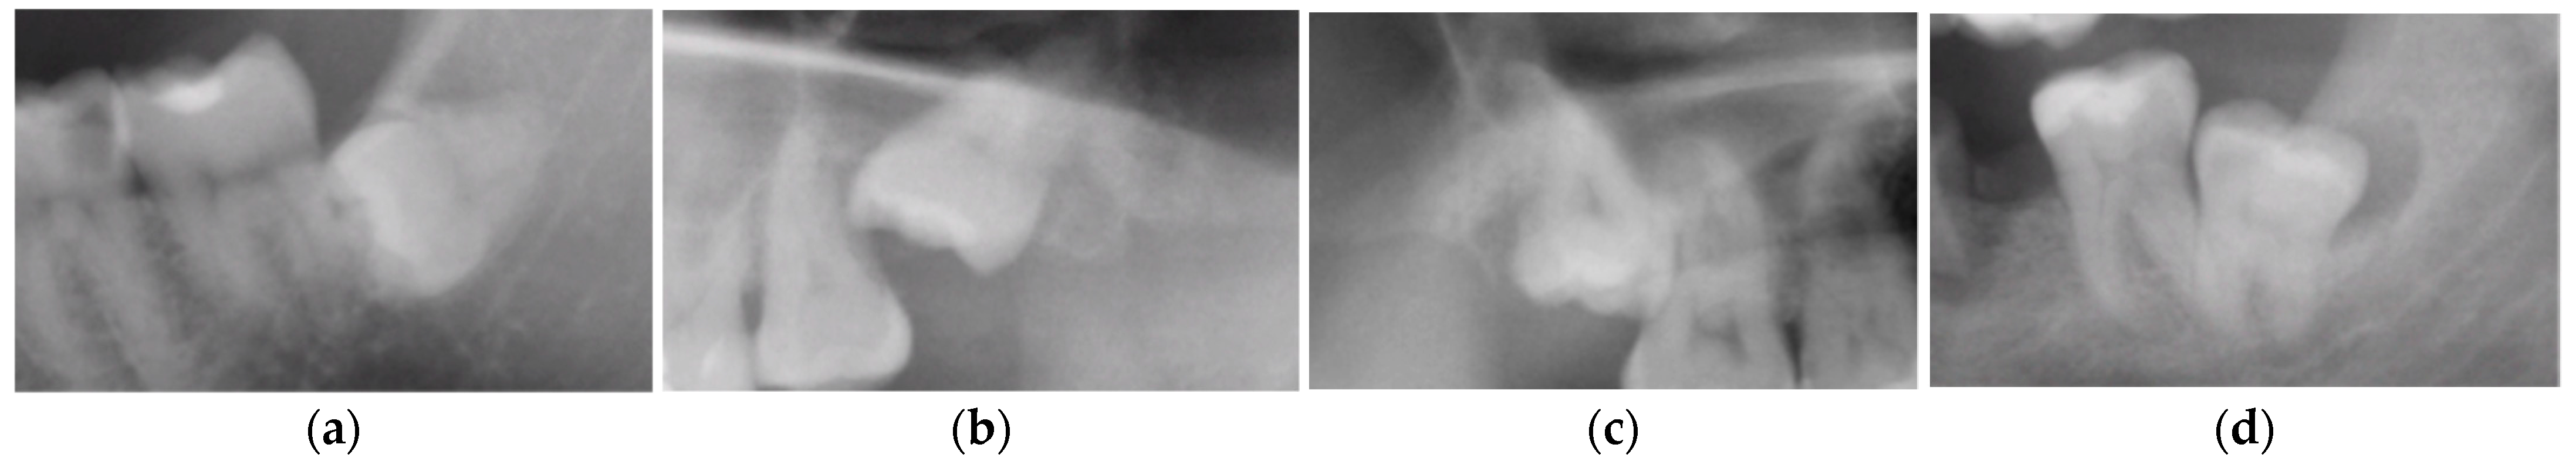

M2s and surrounding tissues were then analyzed for the presence of the following pathologies based on the guidelines by Al Khateeb et al. [24]: (1) caries on the distal surface of the tooth, described as a radiographically clear lesion with no direct contact with the crown of an M3, (2) external root resorption (ERR) on the distal surface of the root, defined as loss of tooth substance, caused by direct contact between M2s and the crown of an M3, (3) alveolar bone loss (ABL) of the alveolar process of the maxilla, or the alveolar part of the mandible distal to M2s, greater than 20% of the length of the distal root (Figure 4).

Figure 4. Radiologic view of pathologies in second molars and adjacent tissues: (a) caries on the distal surface of M2s, (b) external root resorption of the distal root of M2s, (c) bone loss on the distal aspect of M2s.